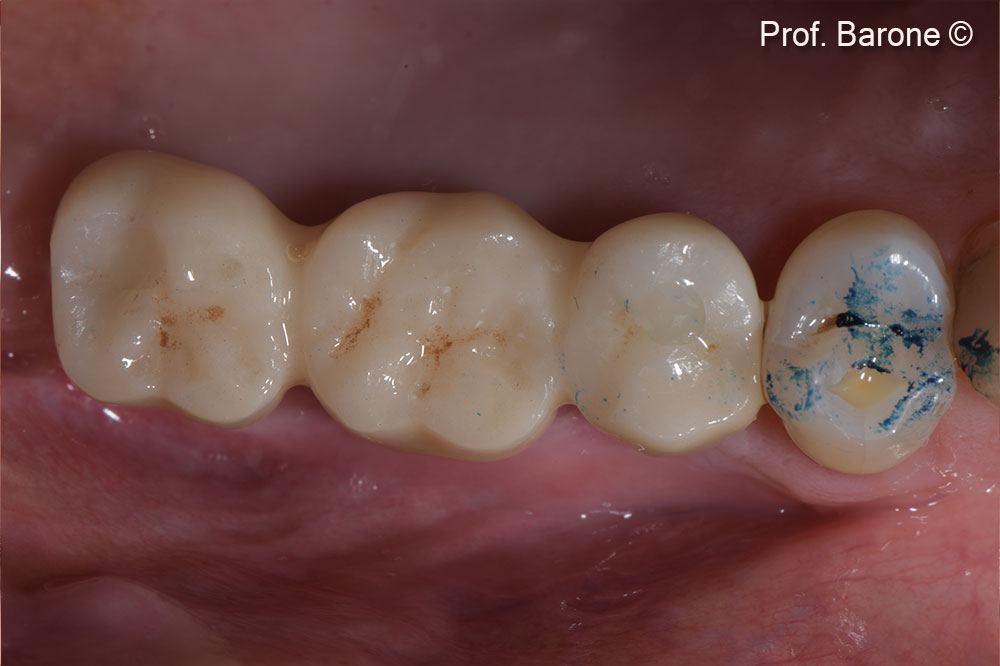

Prosthetic restoration was delivered 3 months after implant placement

Frontal view with the restoration